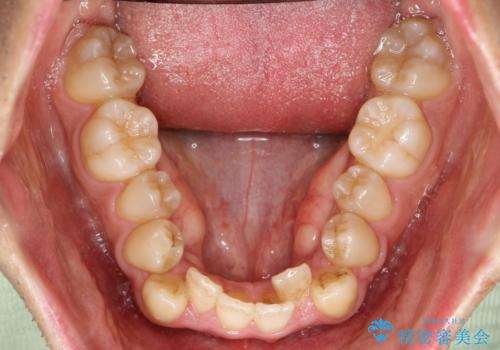

ガタガタの歯並び、八重歯をなおしたい、骨格性下顎前突 カモフラージュ矯正

- 前歯のガタガタと八重歯を治したいということで矯正を希望された患者様です。

骨格的に上顎骨が小さいために相対的に下顎骨が前に出ていたため、歯の傾きなど理想的な仕上がりが難しく、外科矯正ではなく歯列矯正の場合はカモフラージュ矯正になること説明の上、矯正治療を進めることになりました。

上顎は左右5番抜歯、下顎は左右4番抜歯しています。

途中までは下顎は全体にワイヤーをはらずに、セクショナルワイヤーにて治療を進めています。